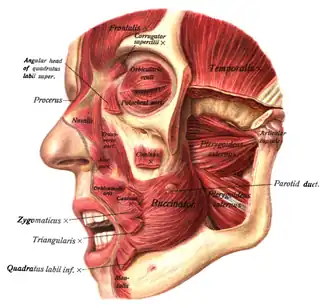

Muscles of the head, face, and neck. (Nasalis labeled at center left.)

Muscles of the head, face, and neck. (Nasalis labeled at center left.) -